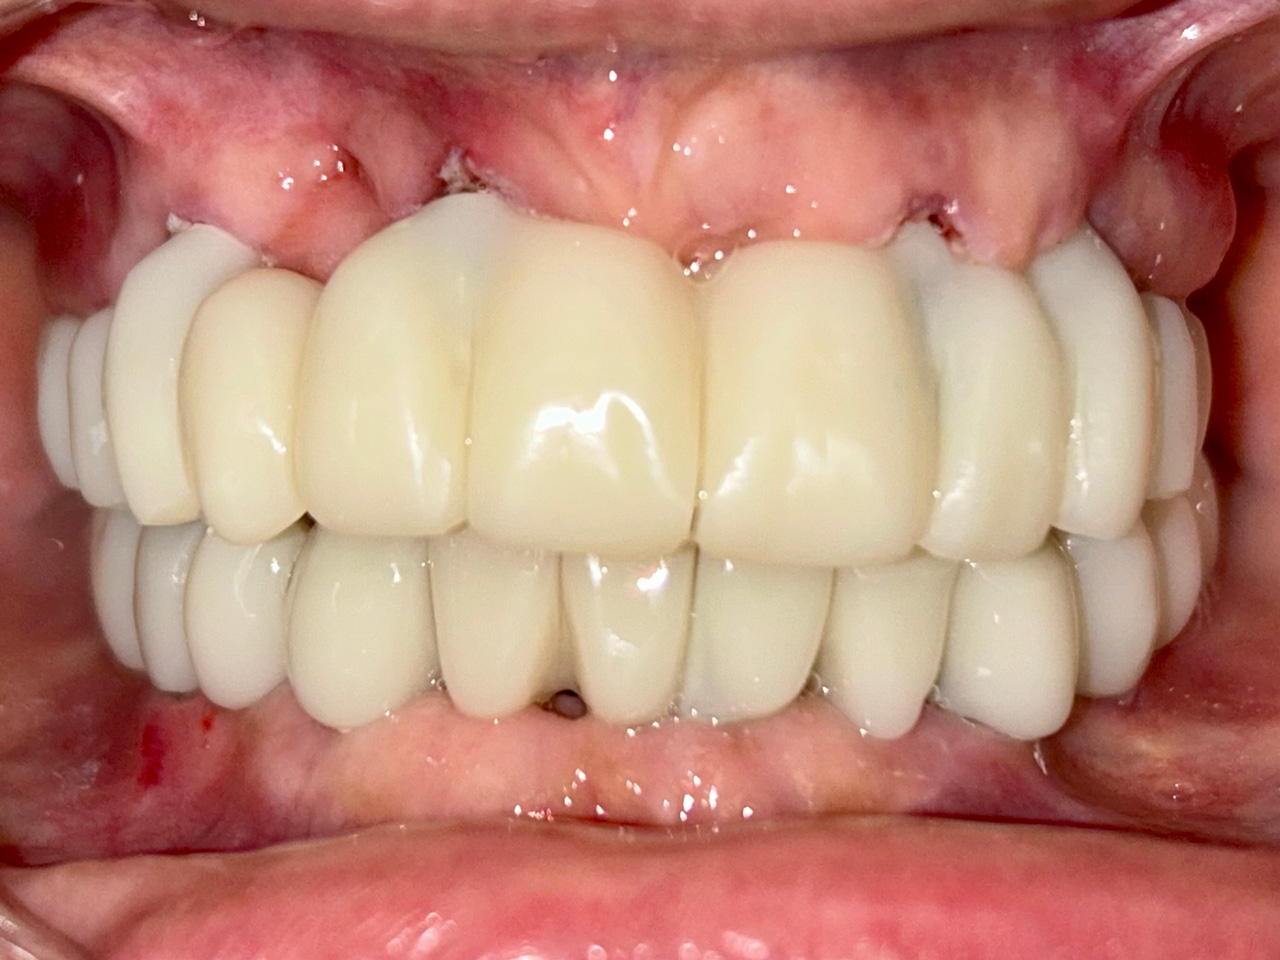

Teljes alsó,felső állcsont helyreállítása azonnal

terhelhető implantátumokkal és porcelán hidakkal.